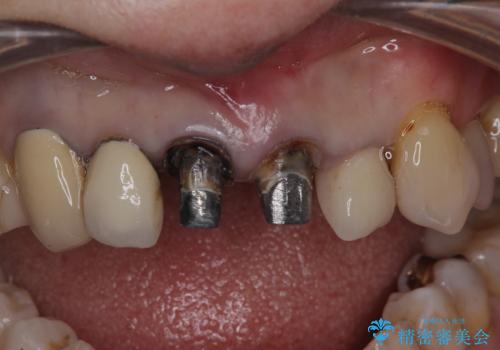

- 他の部位の治療で来院されていましたが、30年以上前に行った前歯のかぶせ物のきわがあっておらず虫歯になってきていました。

神経の治療から念のためやり直ししてからセラミックでかぶせました。

金属の土台が入っていましたがすべて外し、ファイバーコアでやり替えています。